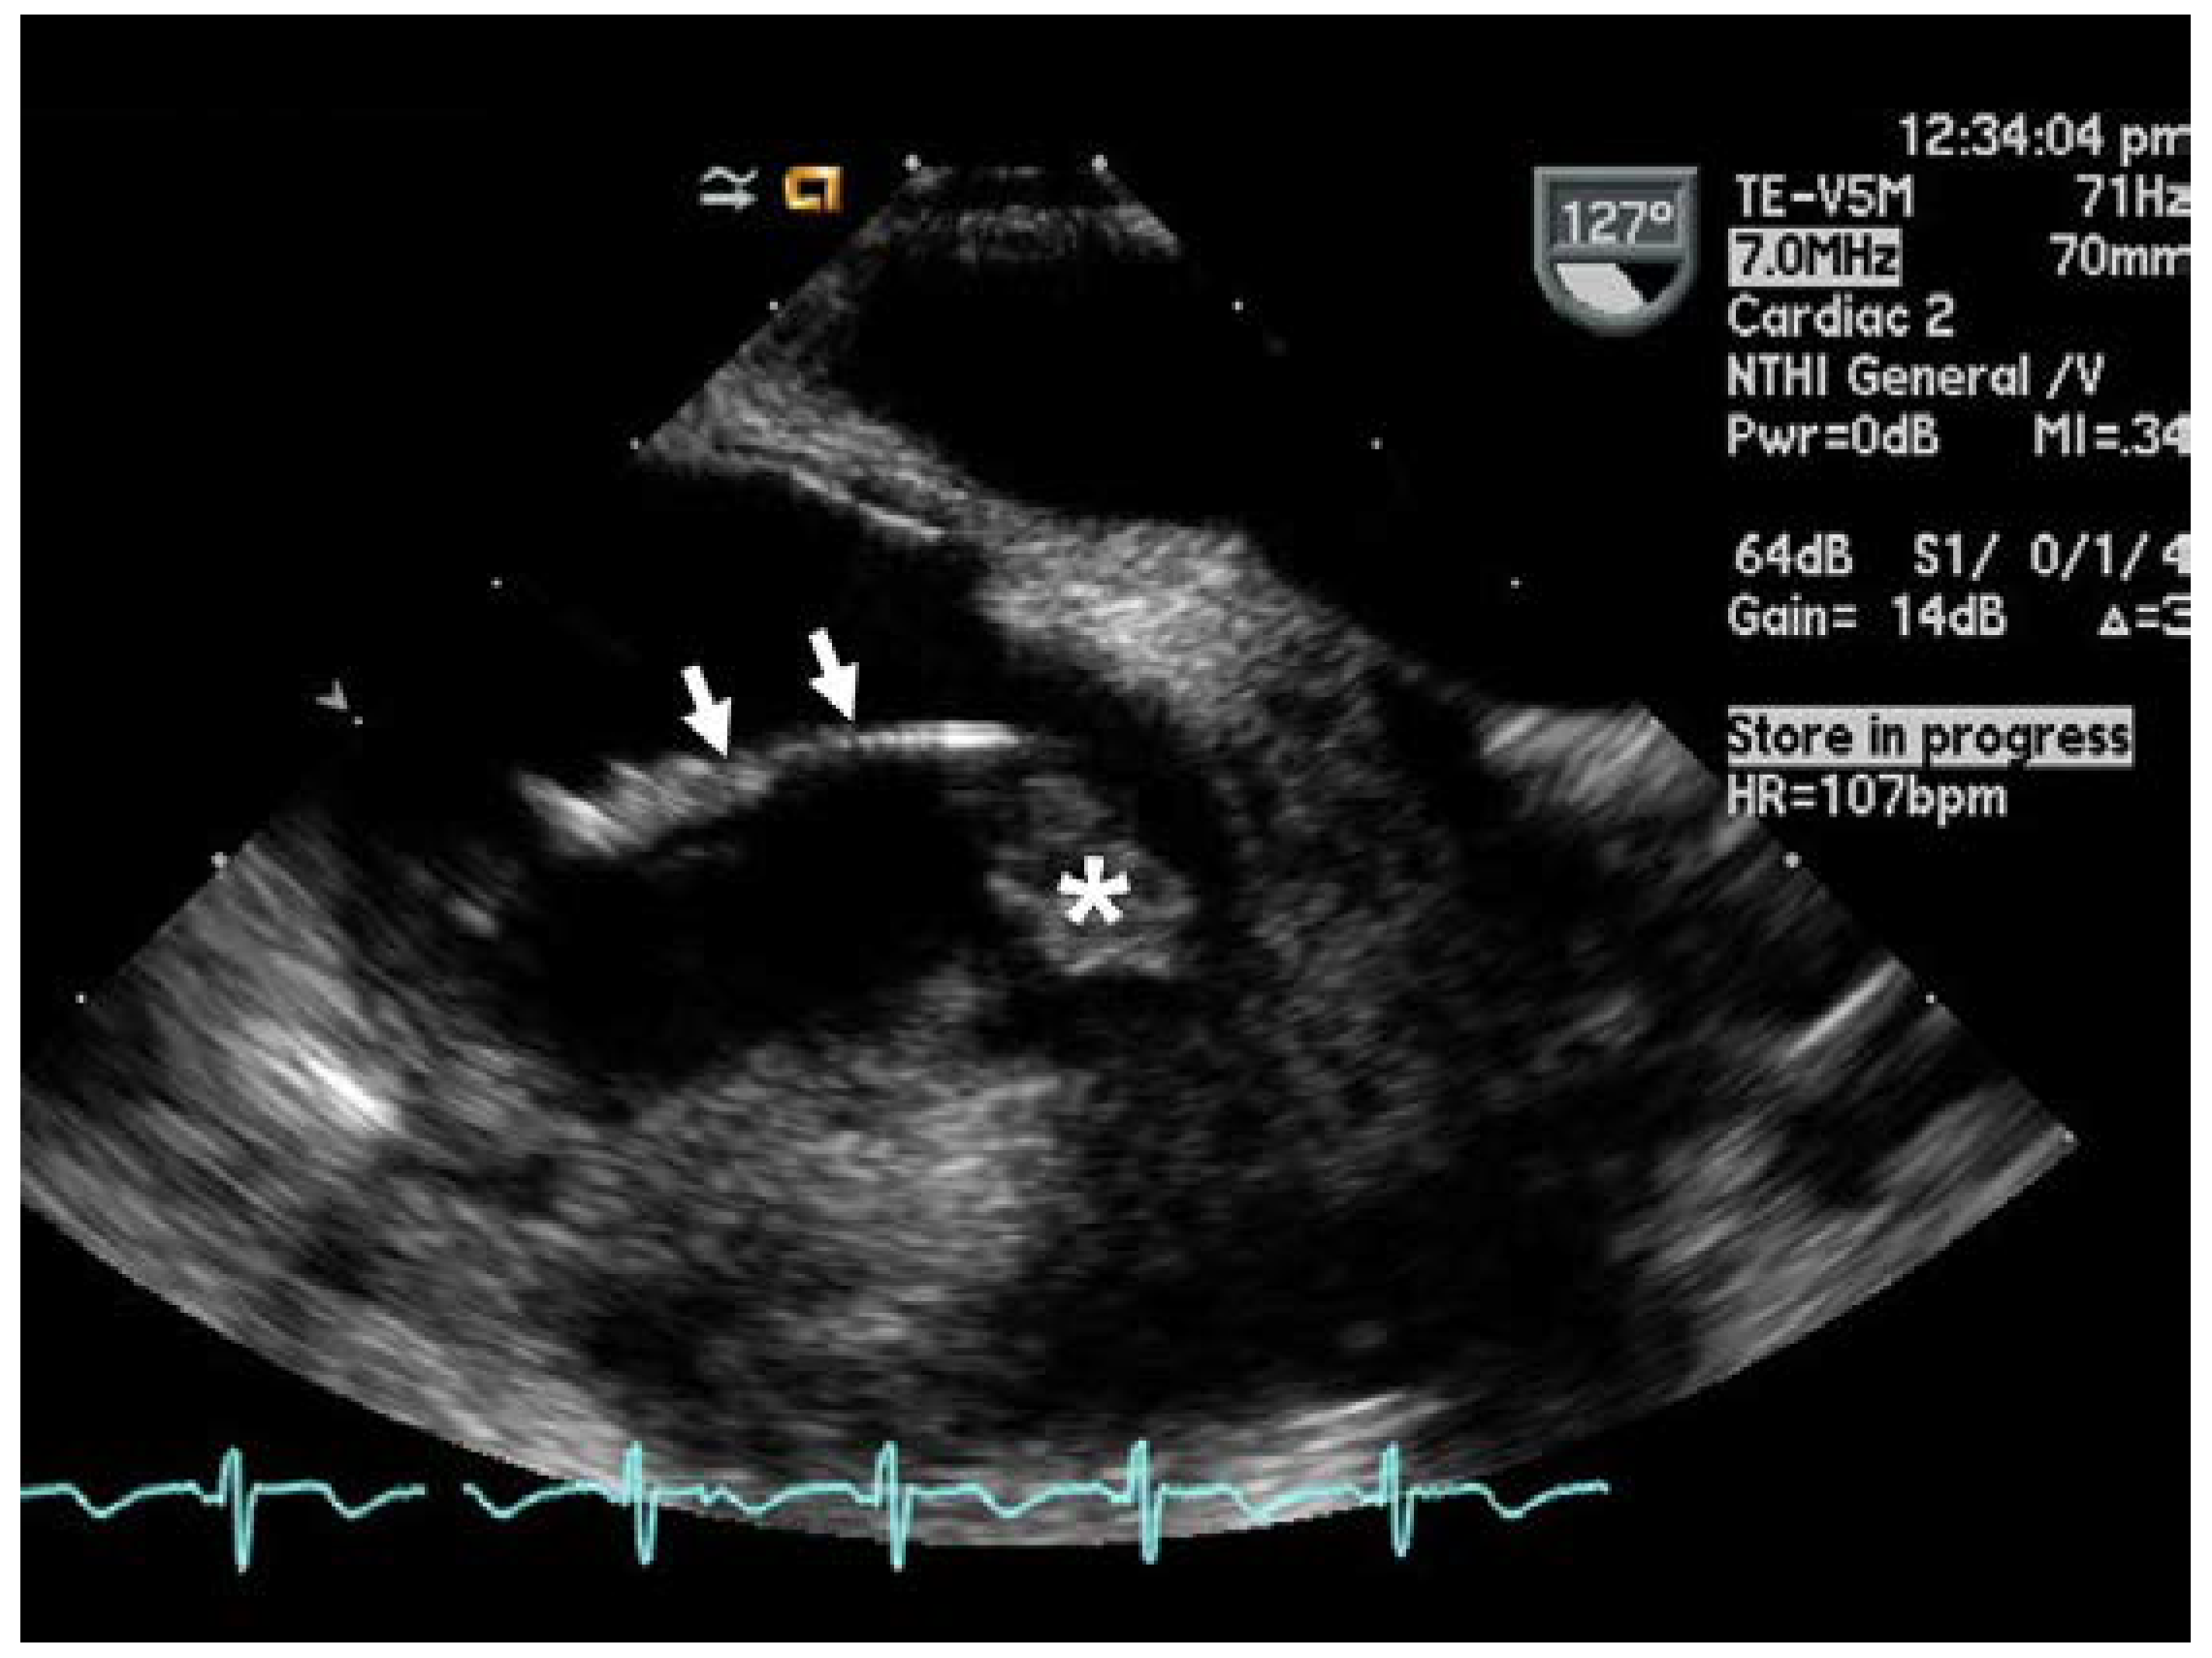

Case presentation